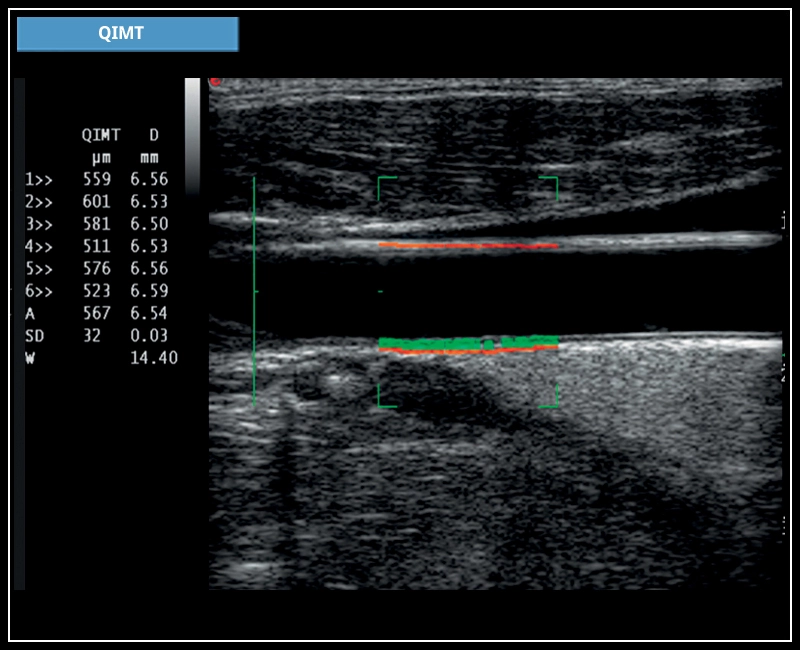

MyLab™X7 - QIMT

MyLab™X7 - QIMT